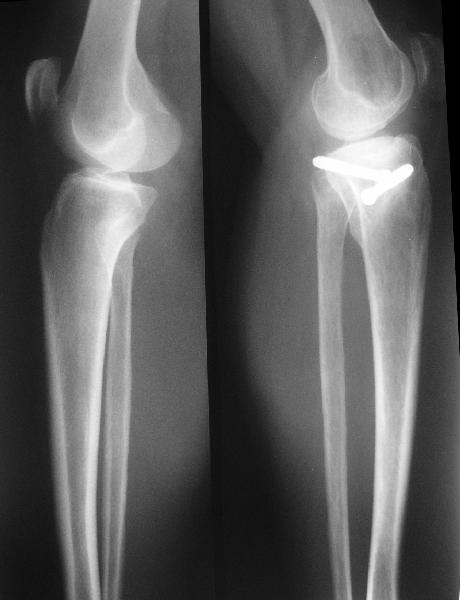

В отделение поступила  пациентка из области, 68 лет.

Травму получила год назад, находилась на лечении  в ЦРБ по поводу перелома

внутреннего мыщелка большеберцовой кости, была вот так прооперирована.

На сегодняшний момент беспокоят боли в области коленного сустава при

ходьбе, движения ограничены, от 180 до 100.

Вложение не в текстовом формате было извлечено&hellip;

Имя     : get_image2.jpg

Тип     : image/jpeg

Размер  : 25567 байтов

Описание: отсутствует

Url     : http://weborto.net:8080/pipermail/ortho/attachments/20090921/92017f40/attachment-0003.jpg